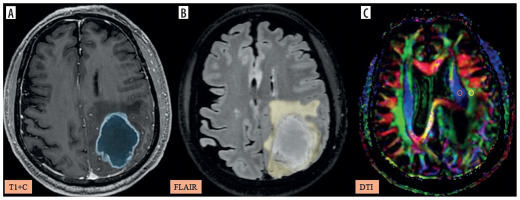

Figure 5

A-C) Patient with high-grade glioma in the left parietal region presenting with right-sided weakness. A) Axial post-contrast T1 image shows the segmented tumour volume (blue). B) Axial fluid-attenuated inversion recovery (FLAIR) image shows the segmented peritumoral oedema (yellow). C) Image describing the calculation of the diffusion tensor image analysis along the perivascular space (DTI-ALPS) index using two regions of interest (ROIs) drawn within the projection (blue) and association (green) fibres in the left periventricular region